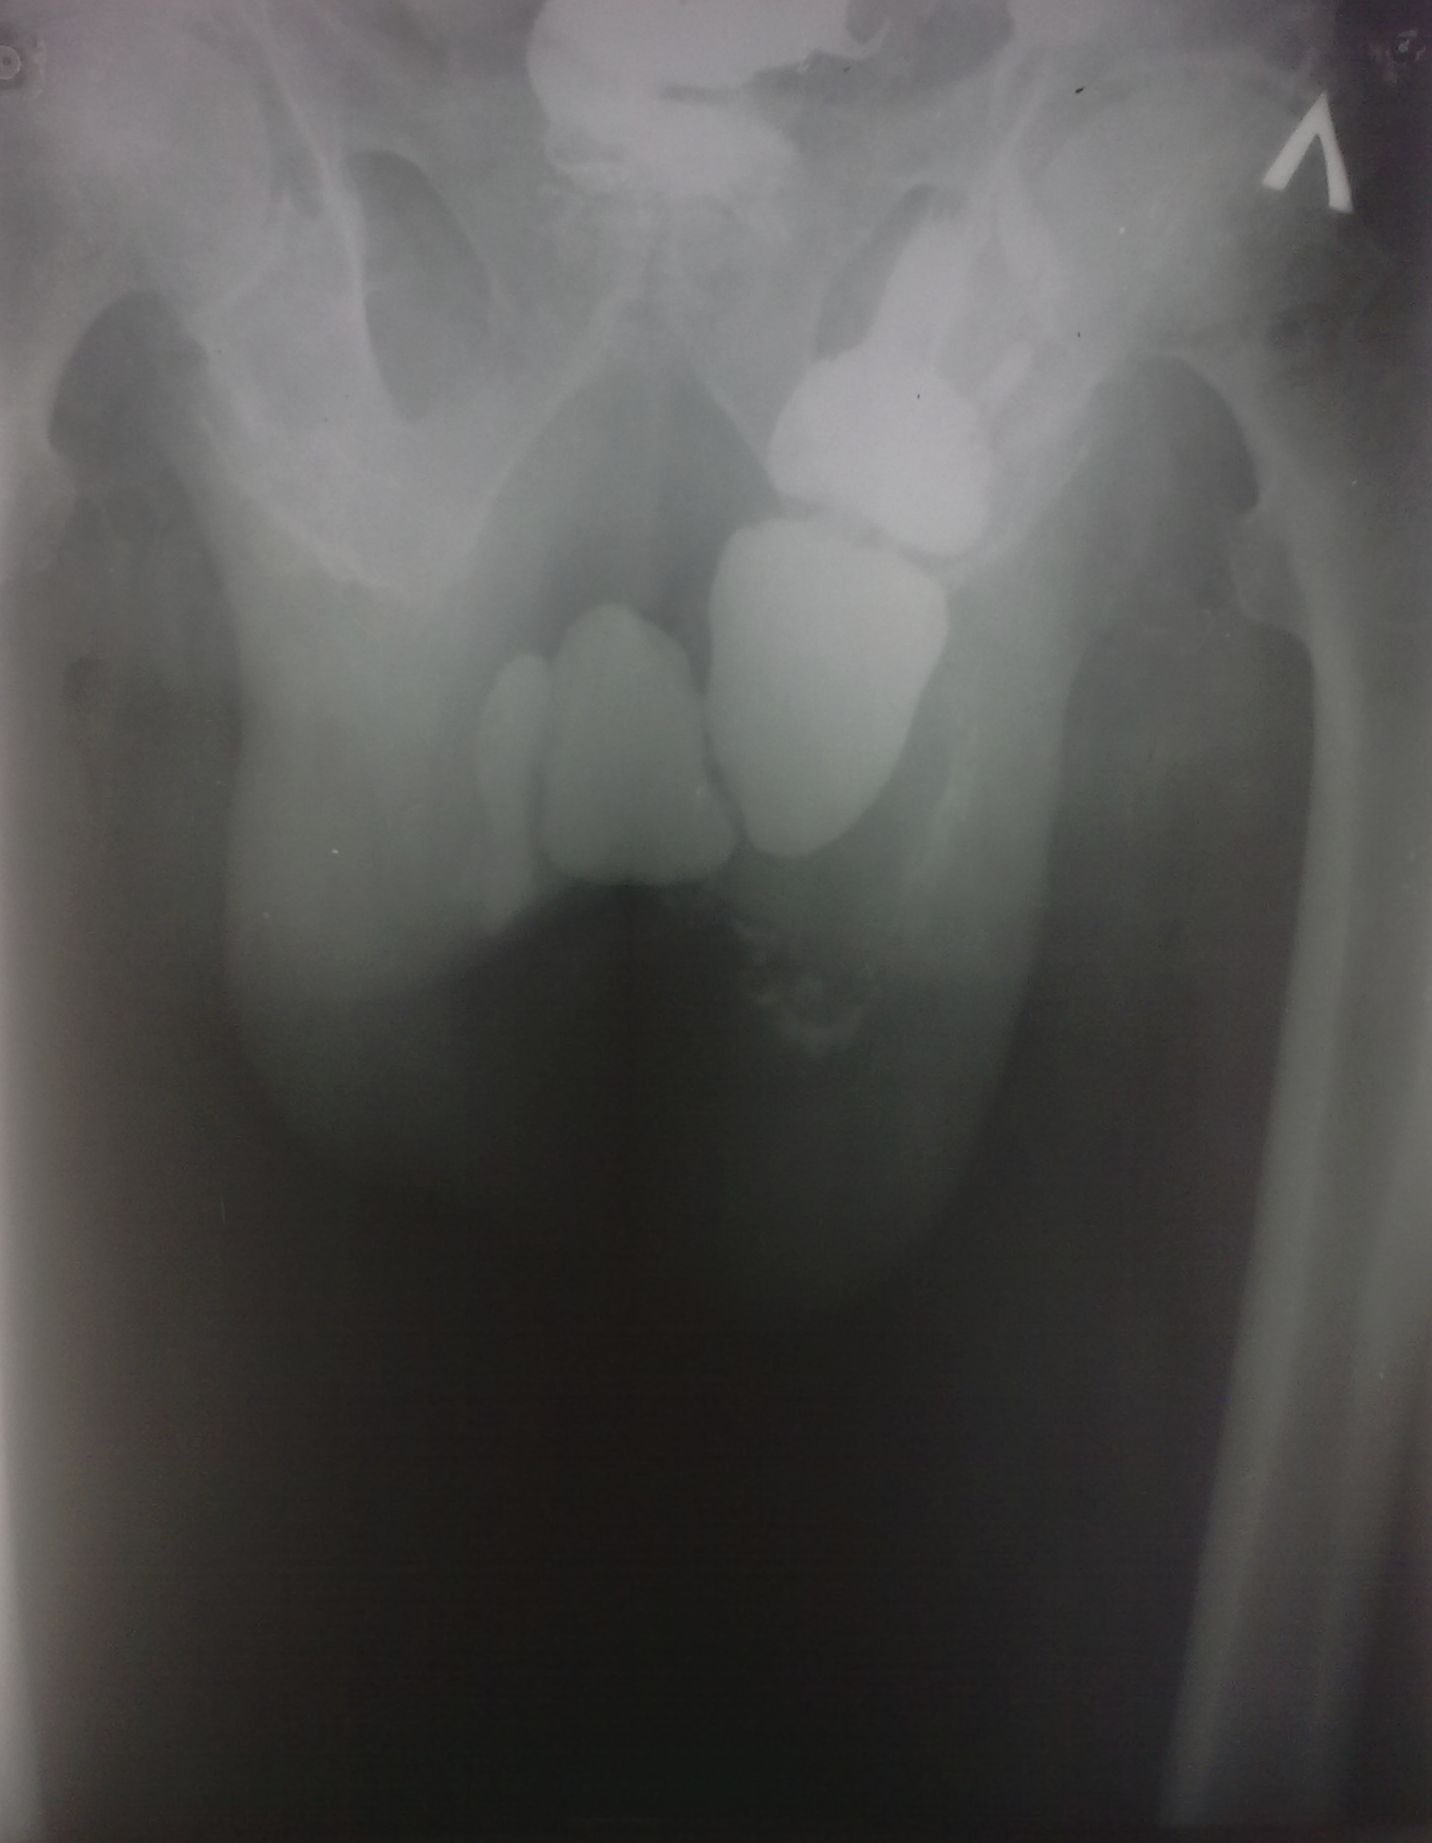

Она не в бедре, там огромный грыжевой мешок с кишками, к сожалению сохранился только этот обзорный снимок. На первое мая решил разобраться в архивах на компьютере...

Там это между ног... Это правая паховая грыжа.

Никак не могу представить процесс проникновения такого топически "непотревоженного" содержимого через паховый канал. В самом крайнем случае - эвентерация на уже оперированном животе. Причем у умственно отсталого, тяжело соматически больного алкоголика из глубокой тундры, так как разом такое не вываливается. В общем - "терзают смутные сомнения"...

Да, такую "бедренную грыжу" видеть не приходилось, да и сейчас не сильно верится..., по всей видимости живот в виде "фартука" наслаивается...

Не верю! Автор сами знаете кто... Почему подвздошная кишка уходит на левое колено?

Могу предположить наличие огромной грыжи белой линии живота, в которую вывалился "ливер" и она болтается спереди в виде "фартука".

На момент исследования болен около 4 лет, операции боялся по этому "носил" до последнего.